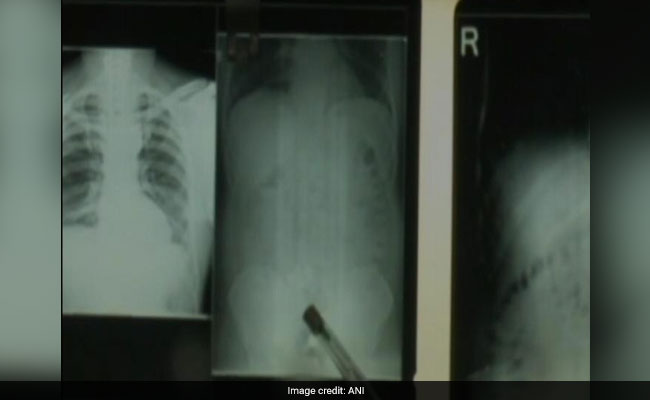

Indian Gold Smugglers Insert Metal In Rectums In Easy-To-Handle Batteries

- Wednesday October 11, 2017

- Tamil Nadu News | Agence France-Presse

Gold smugglers are resorting to increasingly desperate measures to get the metal past customs, officials say, after nearly a dozen people were caught with bullion stashed in their rectums.

Gold Worth Rs 37 Lakh Smuggled In Rectums, Seized At Chennai Airport

Customs officials seized gold worth Rs 37 lakhs on the Chennai International Airport from the rectums of a man and a woman who arrived from Sri Lanka on Friday.